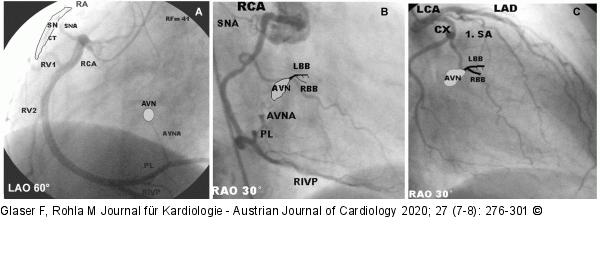

Abbildung 28: Sinusknoten - AV-Knoten Koronarversorgung des Sinus- und des AV-Knotens (schematisch eingezeichnet). A, links: Der Sinusknoten (SN) wird typischerweise durch den ersten, ganz proximal abgehenden, kräftigen RCA-Vorhofast, der AVN über die vom posterolateralen Ast abgehende AV-Knoten Arterie versorgt (AVNA, LAO 60°, von der Herzspitze her betrachtet). B, Mitte: RAO 30° Projektion der RCA-Anatomie. Koronarversorgung des AV-Knotens und des proximalen His-Purkinje-Systems durch die AVNA. Bei Verschluss der RCA proximal der Abgabe der AVNA sind in der Akutphase AV-Blöcke im AVN häufig. C, rechts: Der erste Septumast der LAD nimmt hauptsächlich an der Versorgung des His-Bündels und der proximalen Tawara-Schenkel teil (RAO 30°). Bei Verschluss dieses Astes oder der LAD proximal davor kann deswegen mit infrahissären Blockierungen und Schenkelblöcken (meistens RSB) gerechnet werden. SN: Sinusknoten, SNA: Sinusknotenarterie, AVN: AV-Knoten, AVNA: AV-Knotenarterie, 1. SA: 1. Septumast des LAD, LBB: linker Tawara-Schenkel, RBB: rechter Tawara-Schenkel, RA: rechter Vorhof, CT: Crista terminalis, RV 1, RV 2: rechtsventrikuläre Äste der RCA, PL: posterolateraler Ast, RIVP: Ramus interventricularis posterior. |

Koronarversorgung des Sinus- und des AV-Knotens (schematisch eingezeichnet). A, links: Der Sinusknoten (SN) wird typischerweise durch den ersten, ganz proximal abgehenden, kräftigen RCA-Vorhofast, der AVN über die vom posterolateralen Ast abgehende AV-Knoten Arterie versorgt (AVNA, LAO 60°, von der Herzspitze her betrachtet). B, Mitte: RAO 30° Projektion der RCA-Anatomie. Koronarversorgung des AV-Knotens und des proximalen His-Purkinje-Systems durch die AVNA. Bei Verschluss der RCA proximal der Abgabe der AVNA sind in der Akutphase AV-Blöcke im AVN häufig. C, rechts: Der erste Septumast der LAD nimmt hauptsächlich an der Versorgung des His-Bündels und der proximalen Tawara-Schenkel teil (RAO 30°). Bei Verschluss dieses Astes oder der LAD proximal davor kann deswegen mit infrahissären Blockierungen und Schenkelblöcken (meistens RSB) gerechnet werden. SN: Sinusknoten, SNA: Sinusknotenarterie, AVN: AV-Knoten, AVNA: AV-Knotenarterie, 1. SA: 1. Septumast des LAD, LBB: linker Tawara-Schenkel, RBB: rechter Tawara-Schenkel, RA: rechter Vorhof, CT: Crista terminalis, RV 1, RV 2: rechtsventrikuläre Äste der RCA, PL: posterolateraler Ast, RIVP: Ramus interventricularis posterior. |